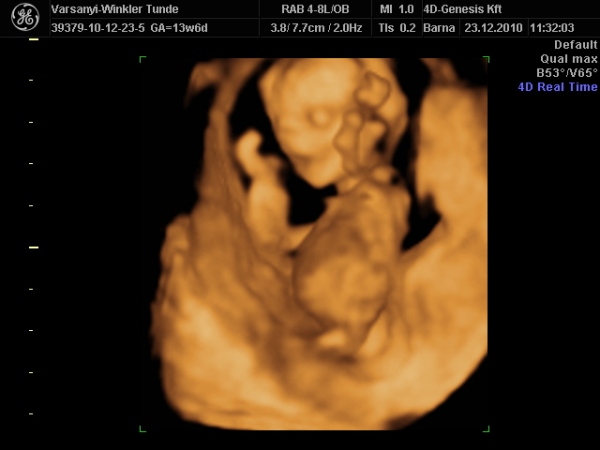

Gondolta, ha arra van a feje, akkor lentről lehet látni valamit a neméből.

Be is terpesztett rendesen, mint egy kis utcalány

Természetesen lánynak is látszott, bár azt mondta, hogy még ne éljük bele magunkat. A férjem le is tört egy kicsit, de nem vallotta volna be.Holnap reggel megyek AFP-re.